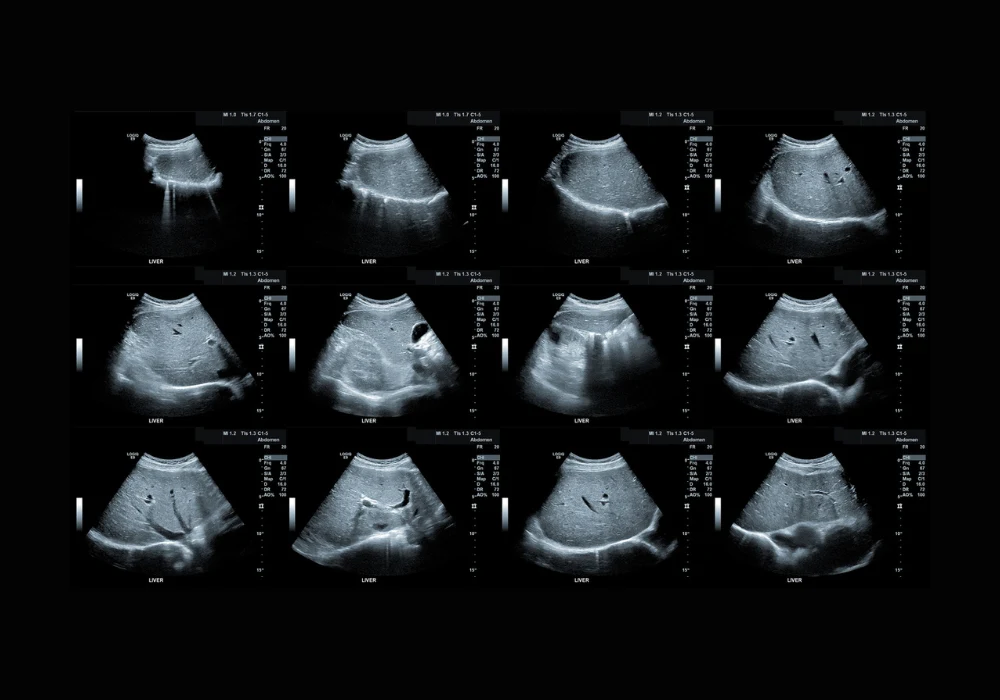

Seven hundred ninety participants were enrolled across 14 hospitals and randomly assigned to derivation and validation cohorts. Each person had ultrasound-derived fat fraction (UDFF) measured using a consistent protocol: a defined region in the right anterior lobe, breath held in neutral and the median of five acquisitions analysed. Examinations took only three minutes, supporting real-world hospital workflow. Reference standards included MRI proton density fat fraction (MRI-PDFF), liver histopathology and proton spectroscopy, enabling comparison against both imaging and tissue-based benchmarks within a short interval after ultrasound.

UDFF aligned closely with each reference method. Agreement with MRI-PDFF was strong, and UDFF values rose stepwise with histological severity from no steatosis to advanced grades. Reproducibility was excellent, with tightly matched measurements on repeat testing and strong alignment between readers with different levels of experience. Against clinical indices used in primary or metabolic care, UDFF showed higher diagnostic performance for all binary tasks evaluated, reinforcing its value as a frontline imaging measure rather than a secondary risk score.